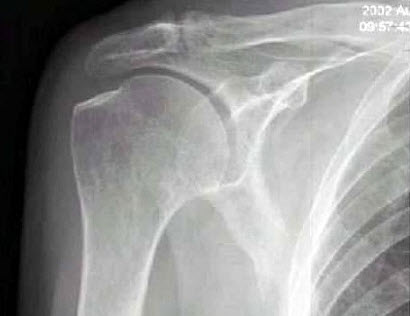

右肩关节活动受限1年多,体检发现右手上抬不能,后展受限,行右肩关节摄片如图示,最可能的诊断是()

A.正常右肩关节